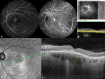

Figures